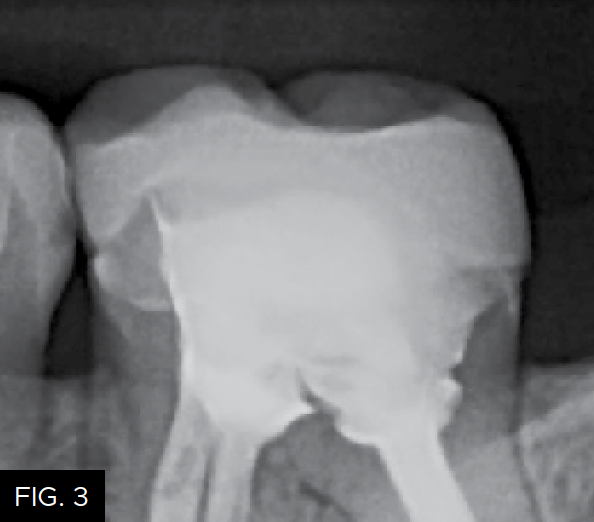

The patient shown in FIG. 1 presented with radiographic decay (FIG.2 and 3) on the distal surfaces of tooth numbers 19 (36) and 21 (34).